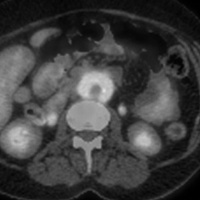

Инфекции мочевыводящих путей – состояние инфицирования мочевыводящего тракта микрофлорой, которая вызывает его воспаление.Различают инфекцию верхних (пиелонефрит) и нижних мочевых путей (цистит, простатит, уретрит) по наличию или отсутствию симптомов (симптоматическую или бессимптомную бак-териурию), по происхождению инфекции (внебольничную или нозокомиальную), осложненные и неосложненные.

Осложненные инфекции сопровождаются функциональными или анатомическими аномалиями верхних или нижних мочевых путей.